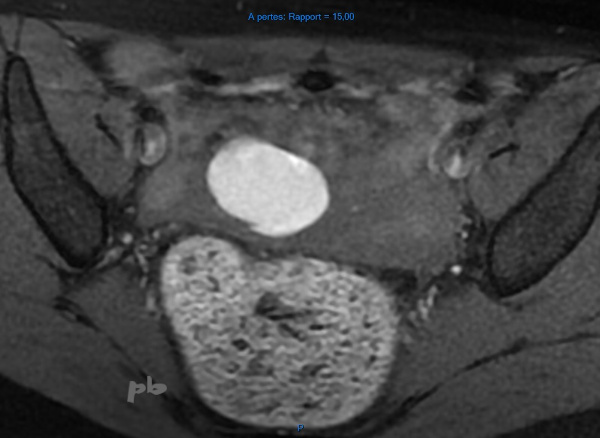

IRM ax T1 fatsat

Image hypersignal T1 chez une patiente porteuse d’un syndrome de Turner.

De rares cas sont décrits dans la littérature, en cas de mosaïque XO/XX.

Un kyste endométriosique peut également être rencontré chez une patiente ménopausée.